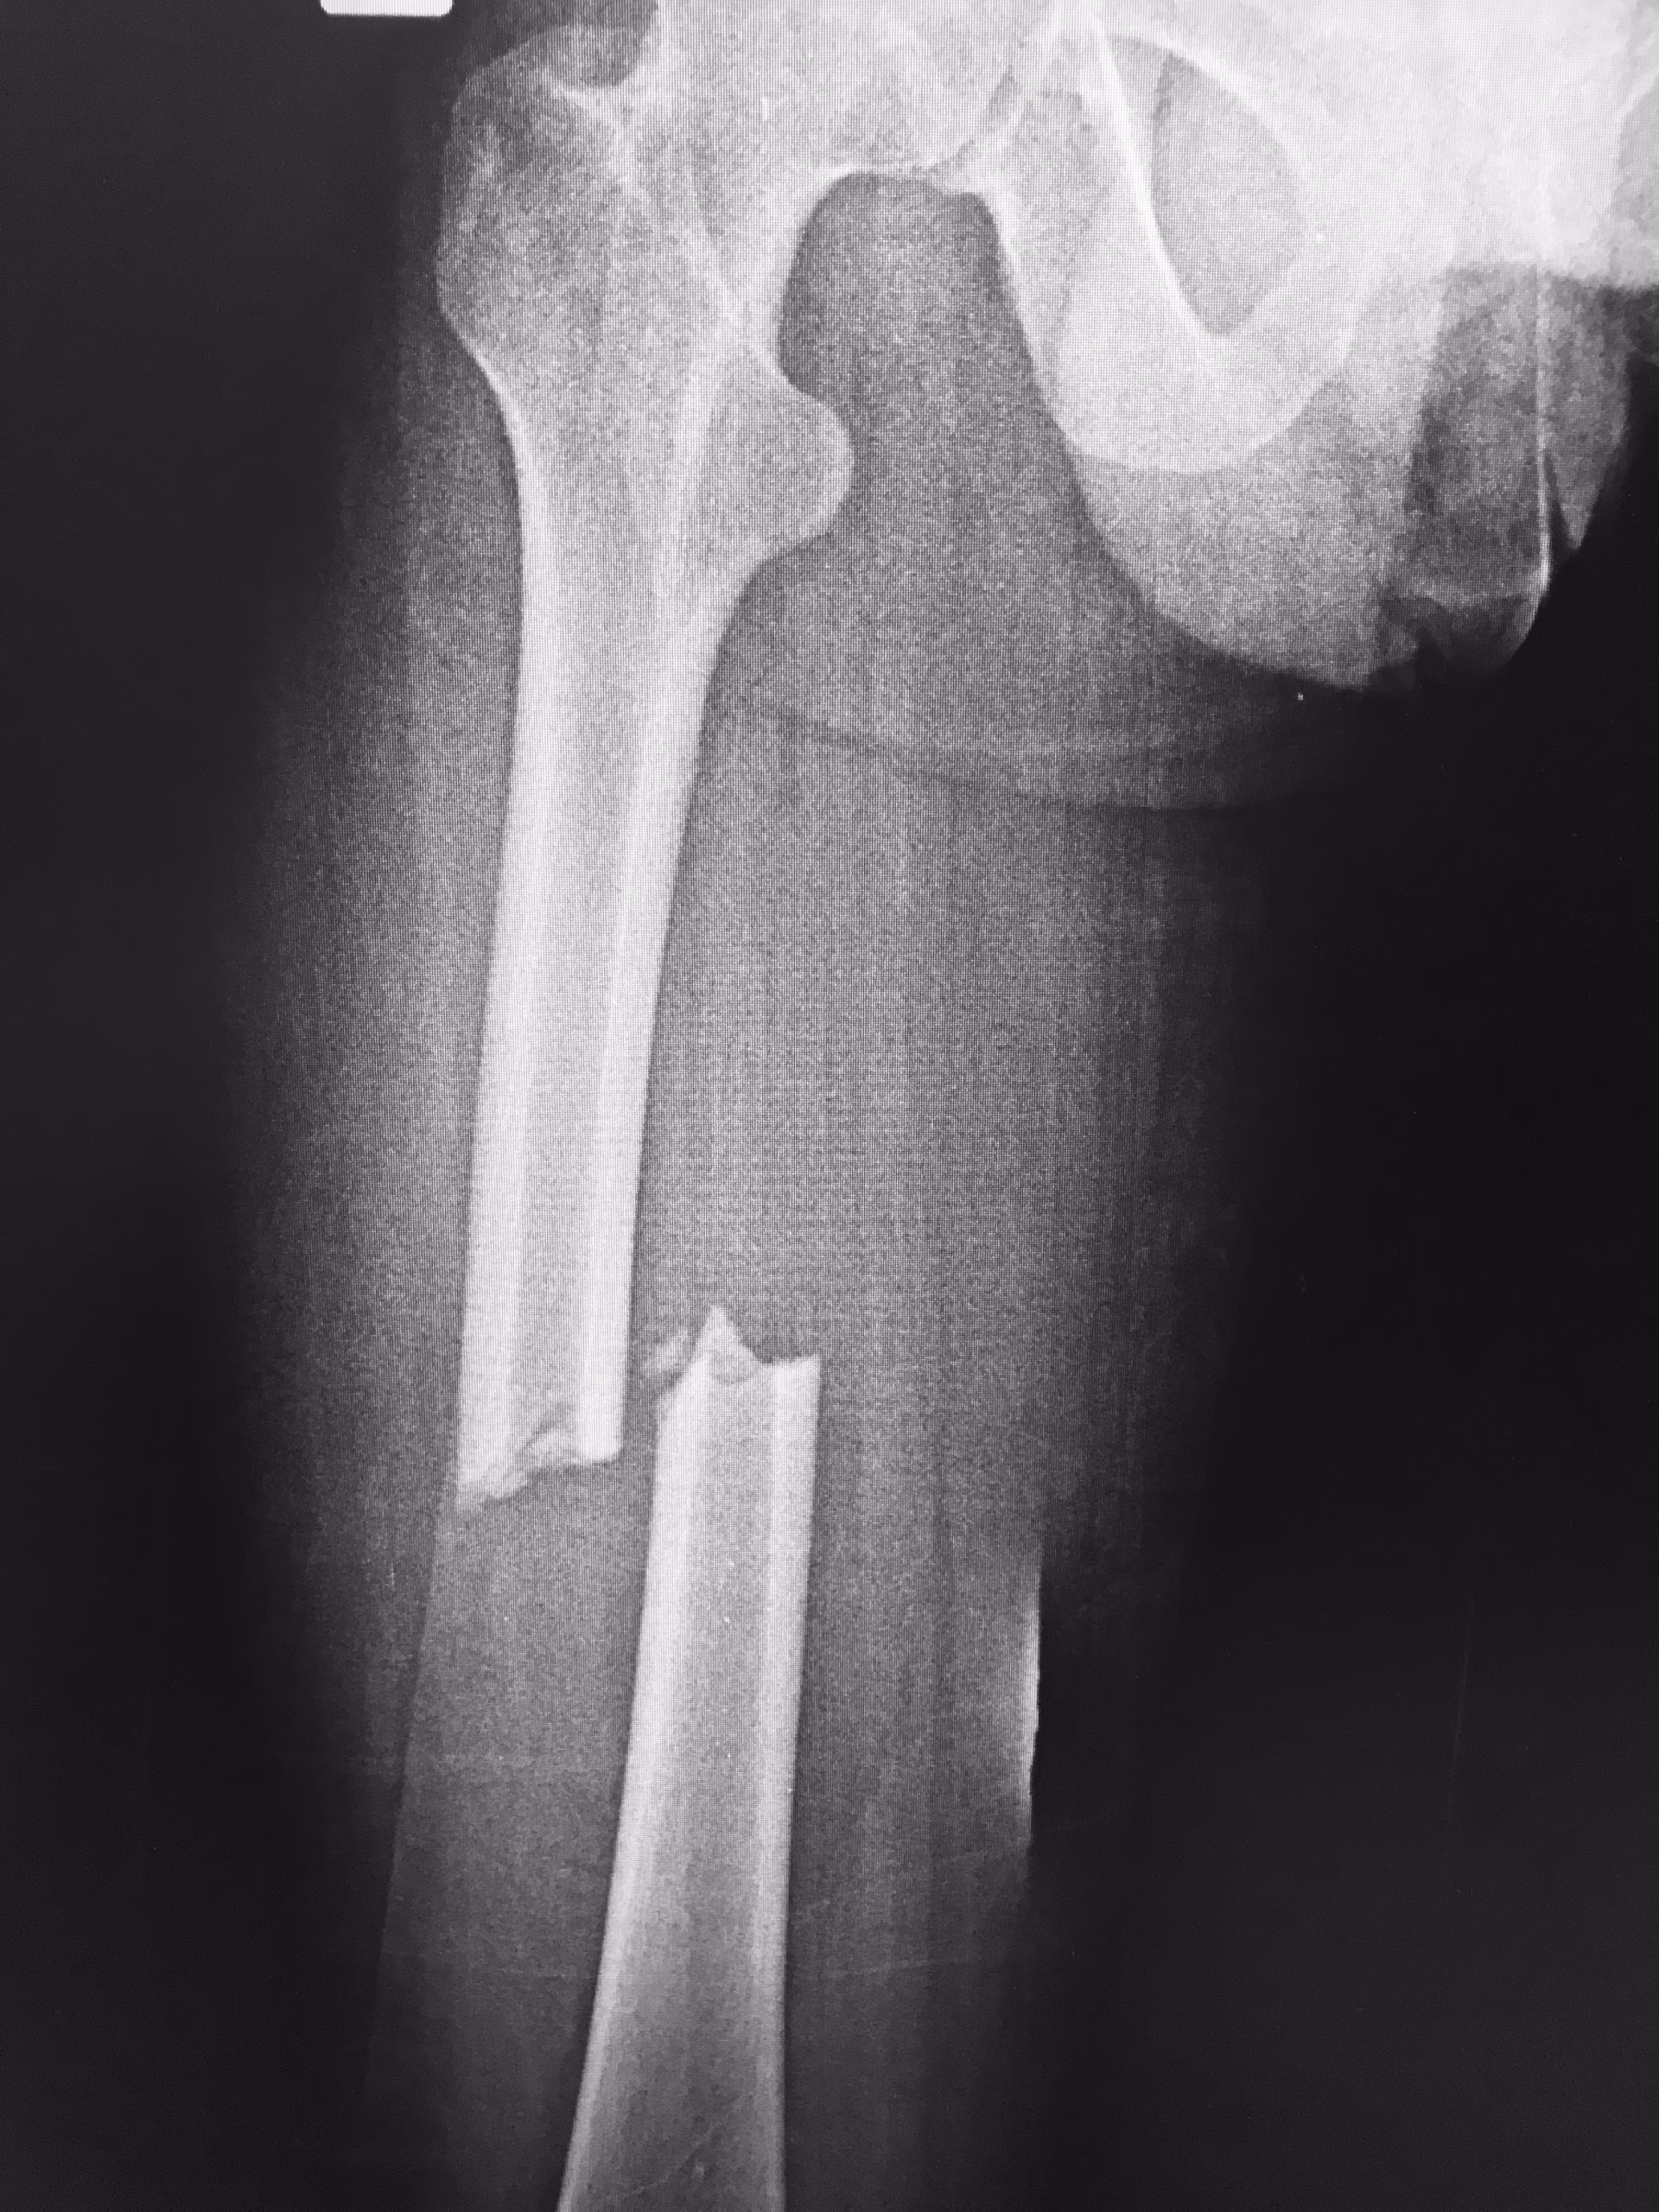

Quant au bassin, ses fractures sont fréquemment liées à des chutes de hauteur ou des accidents de la route, et peuvent affecter la stabilité du tronc et des membres inférieurs.

En présence d’une fracture du bassin, limitez les déplacements, installez la victime dans une position neutre si possible, et attendez les paramédics. Si la personne ne sent plus ses jambes ou les contrôle mal, cela peut signaler une atteinte neurologique.

Une fracture du bassin peut s’accompagner d’un hématome, de saignements urinaires, ou d’une incapacité à mobiliser les jambes. Le moindre déplacement peut aggraver une hémorragie interne ou des dommages aux organes voisins.